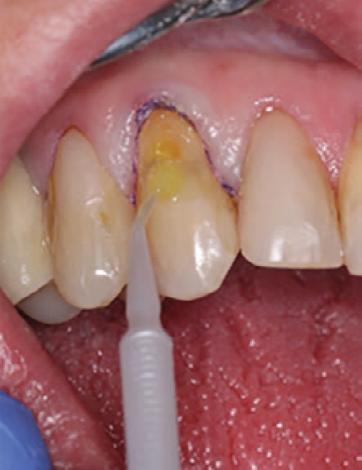

To improve isolation and soft tissue access, a retraction cord was placed before initiating the procedure (Fig. 2). The tooth was evaluated using a caries indicator dye (Kuraray Noritake Dental), helping to identify any remaining infected tissue beneath the dislodged composite (Fig. 3). Decay removal was completed with a diamond bur, and the enamel was bevelled using a starburst pattern to enhance aesthetic blending (Fig. 4). This preparation design was chosen for visual integration rather than bond strength enhancement.

Etching and Bonding

Selective etching of the enamel was performed using a phosphoric acid etchant, followed by rinsing and air drying (Fig. 5). CLEARFIL™ Universal Bond Quick 2 was then applied according to the manufacturer’s protocol: a three second application, gentle airdrying, and light-curing for 20 seconds (Fig. 6).

4. Preparation of the lesion completed with diamond bur and starburst beveling pattern to enhance aesthetic blending.

Figure 5. Selective etching of the enamel at the margins.

Figure 6. Application of CLEARFIL Universal Bond Quick 2 following selective etching of the enamel margins.